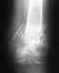

МРТ коленного сустава, заключение: дистрофические изменения заднего рога внутреннего мениска. С учетом перенесеной травмы и сохранившимися признаками отека костного мозга "patella bipartita" травматического генеза. Синовиит. Что делать дальше?